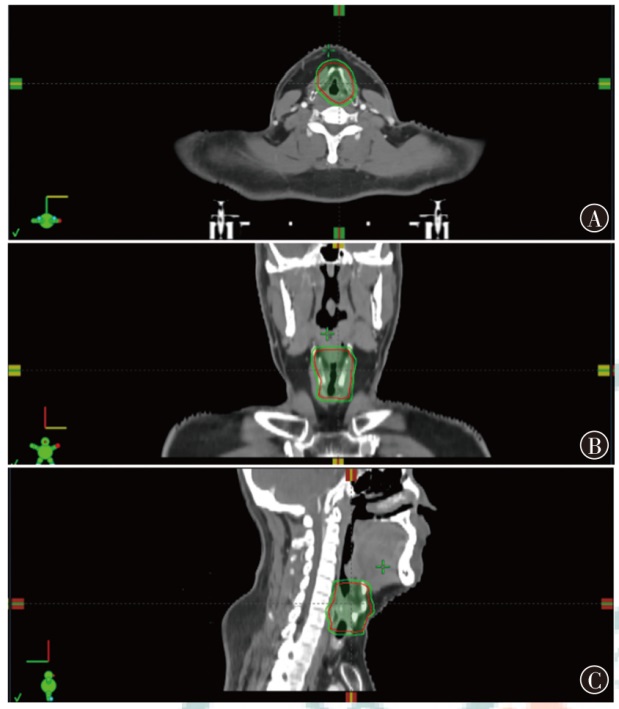

Objective To investigate the dosimetric characteristics of intensity modulated proton therapy (IMPT) and photon volumetric modulated arc therapy (VMAT) in typical head and neck malignant tumors. Methods Three types of typical head and neck tumors (nasopharyngeal carcinoma, parotid gland carcinoma, laryngeal carcinoma) treated at Shandong Cancer Hospital and Institute from December 2023 to December 2024 were taken as research subjects. IMPT and VMAT radiotherapy plans were created according to clinical prescription requirements of target and organs at risk limits respectively. The conformity index (CI), homogeneity index (HI) and gradient index (GI) for target coverage of two radiotherapy plans were evaluated for 3 patients, as well as the dosimetric indicators of organs at risk. Results The CI of IMPT for nasopharyngeal carcinoma, parotid gland carcinoma and laryngeal carcinoma were 0.70, 0.72 and 0.67, respectively. The HI were 0.11, 0.08 and 0.08, respectively. The GI were 3.08, 2.49 and 3.75, respectively. The CI of VMAT plans were 0.77, 0.82 and 0.91, respectively. The HI were 0.12, 0.10 and 0.04, respectively. The GI were 3.67, 2.63 and 3.45, respectively. The results showed that CI of IMPT plan was slightly lower than that of VMAT plan, and HI of IMPT plan was comparable to that of VMAT plan, the GI of the IMPT plan for patients with nasopharyngeal carcinoma and parotid gland carcinoma was lower than that of the VMAT plan, and the GI of the IMPT plan for patient with laryngeal carcinoma was higher than that of the VMAT plan, and all were within the clinically acceptable range. The IMPT plan has demonstrated significant dose advantages in the treatment of nasopharyngeal carcinoma, parotid gland carcinoma and laryngeal carcinoma. For patient with nasopharyngeal carcinoma, the IMPT plan reduced the Dmax of the left and right crystals by 54.1% and 50.4%, respectively, compared to VMAT plan, and reduced the Dmean of the oral and laryngeal tissues by 40.5% and 49.6%, respectively. For patient with parotid gland carcinoma, IMPT plan reduced the Dmax of the brainstem and spinal cord by 66.2% and 40.5%, respectively, compared to VMAT plan. For patient with laryngeal carcinoma, IMPT reduced spinal cord Dmax by 77.0%, while thyroid cartilage Dmean increased by 8.0% compared to VMAT plan. For the additional dose in the patients' body, taking the absolute volumes occupied by the prescribed dose areas of 10%, 30%, and 50% in the patients' body as examples, IMPT plan of nasopharyngeal carcinoma patient decreased by 29.7%, 29.6%, and 34.9% compared to VMAT plan, respectively. IMPT plan of parotid gland carcinoma patient decreased by 61.0%, 39.7%, and 17.4% compared to VMAT plan, respectively. IMPT plan of laryngeal carcinoma patient decreased by 63.9%, 31.7%, and 4.1% compared to VMAT plan, respectively. Conclusions Compared with VMAT plan, IMPT plan can effectively reduce the irradiation dose of most organs at risk near the target of head and neck tumors, but the dose of string organs close to the target area may be higher, which needs attention.